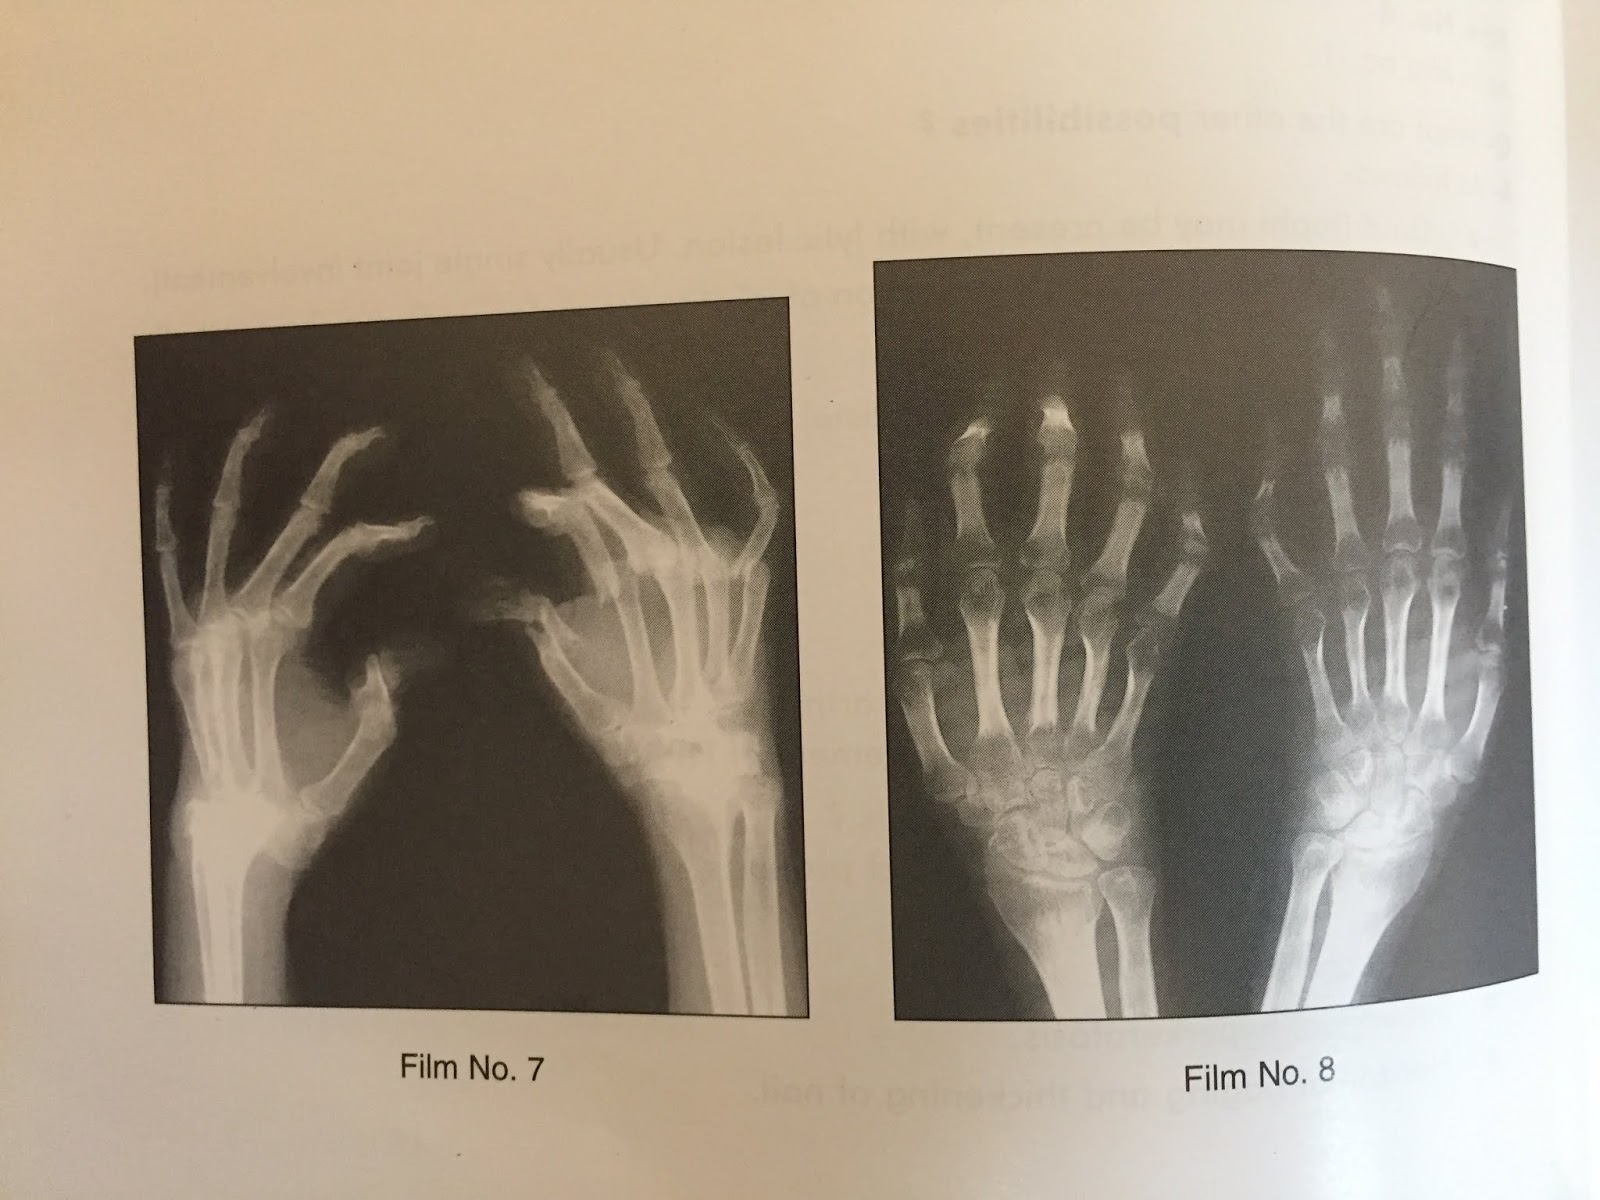

Psoriatic Arthritis Xray Hand. Up to 30% of patients with psoriasis develop psoriatic arthritis (psa) resulting,. psoriasis is a common skin disease. Symptoms of psa include joint pain, stiffness, and swelling which flare and subside. The erosion or destruction of bone tissue, known as osteolysis. rheumatoid arthritis (ra) and psoriatic arthritis (psa) are common causes of chronic inflammatory diseases of the hand. accurate diagnosis and therapeutic intervention at an early stage is paramount for the management of rheumatoid. psoriatic arthritis (psa) is a type of inflammatory arthritis that affects some people with the autoimmune skin condition psoriasis. Up to 30% of patients with psoriasis develop psoriatic arthritis (psa) resulting,. Spaces narrowing in a joint. Copyright © 2015 the korean dermatological. Treatment for the condition is aimed at reducing inflammation, managing symptoms, and improving quality of life. psoriasis is a common skin disease.

The erosion or destruction of bone tissue, known as osteolysis. Up to 30% of patients with psoriasis develop psoriatic arthritis (psa) resulting,. psoriasis is a common skin disease. Copyright © 2015 the korean dermatological. Up to 30% of patients with psoriasis develop psoriatic arthritis (psa) resulting,. Spaces narrowing in a joint. psoriasis is a common skin disease. psoriatic arthritis (psa) is a type of inflammatory arthritis that affects some people with the autoimmune skin condition psoriasis. Symptoms of psa include joint pain, stiffness, and swelling which flare and subside. accurate diagnosis and therapeutic intervention at an early stage is paramount for the management of rheumatoid.

Psoriatic Arthritis Xray Hand psoriasis is a common skin disease. Treatment for the condition is aimed at reducing inflammation, managing symptoms, and improving quality of life. psoriasis is a common skin disease. rheumatoid arthritis (ra) and psoriatic arthritis (psa) are common causes of chronic inflammatory diseases of the hand. psoriasis is a common skin disease. Up to 30% of patients with psoriasis develop psoriatic arthritis (psa) resulting,. The erosion or destruction of bone tissue, known as osteolysis. Copyright © 2015 the korean dermatological. Spaces narrowing in a joint. accurate diagnosis and therapeutic intervention at an early stage is paramount for the management of rheumatoid. Symptoms of psa include joint pain, stiffness, and swelling which flare and subside. Up to 30% of patients with psoriasis develop psoriatic arthritis (psa) resulting,. psoriatic arthritis (psa) is a type of inflammatory arthritis that affects some people with the autoimmune skin condition psoriasis.